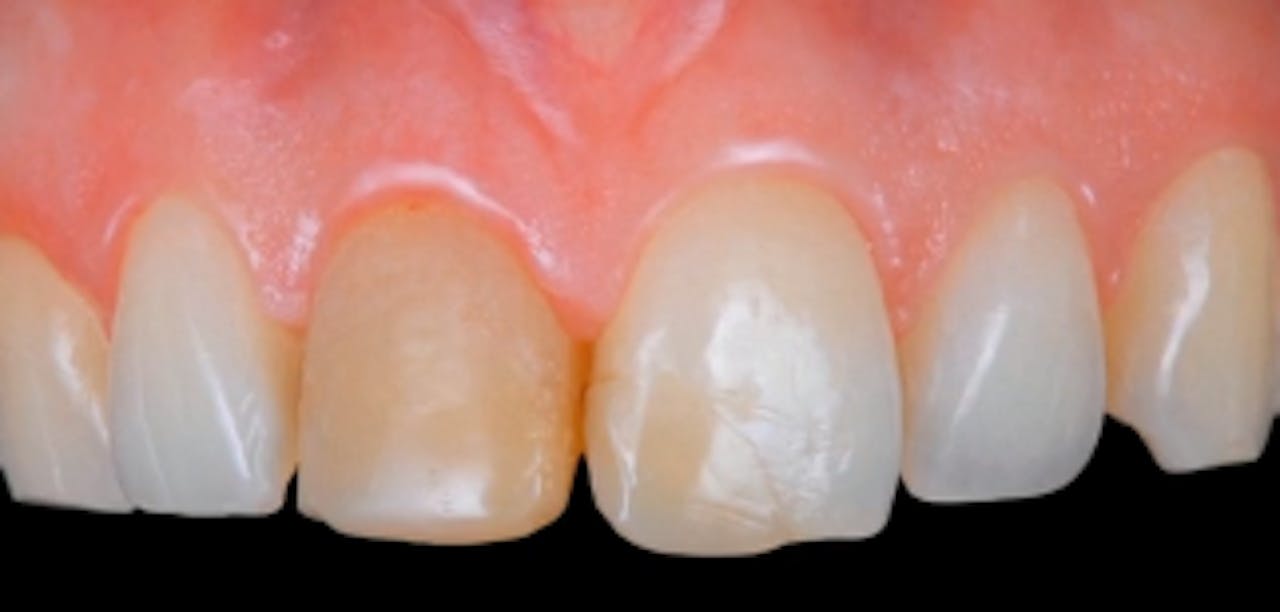

AllCeramic Solutions On Teeth & Implants gIDE Dental Institute Gide Dental Reviews • 550+ clinical videos on web and app • new dental videos added. Clinical videos, expert interviews, live broadcasts over. Evidence based video education at its best. Premiere provider of online dental education. Learn from the world's most trusted faculty and advance your skills with gide. Gide dental | 280 followers on linkedin. 31,762 likes · 74 talking about this. Gide Dental Reviews.